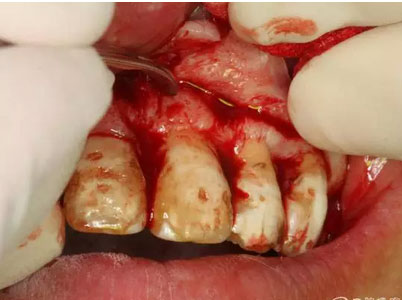

圖11.逐漸去骨薄如蟬翼的骨壁,暴露出完整的囊壁

圖12.暴露出的完整囊壁,真夠大!